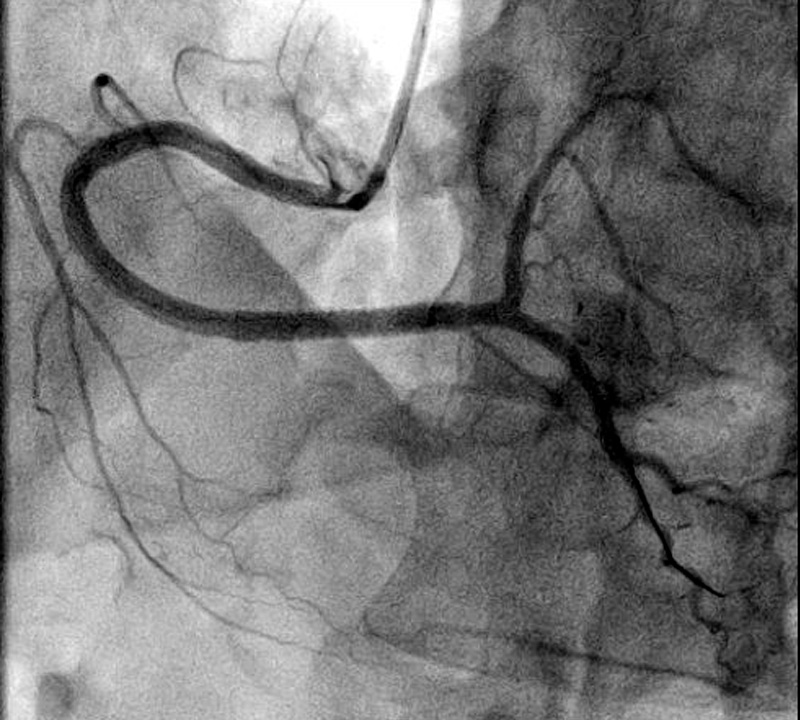

Ангиограмма:

Острая 100% (TIMI 0) окклюзия ПКА, выполнено ЧКВ